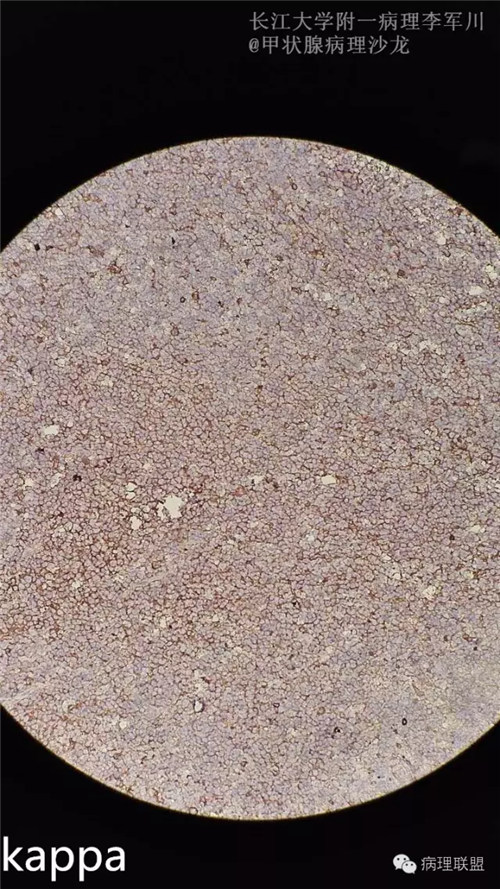

甲状腺病变中的MALT?

女,40余岁,右侧甲状腺肿块,直径约3cm。